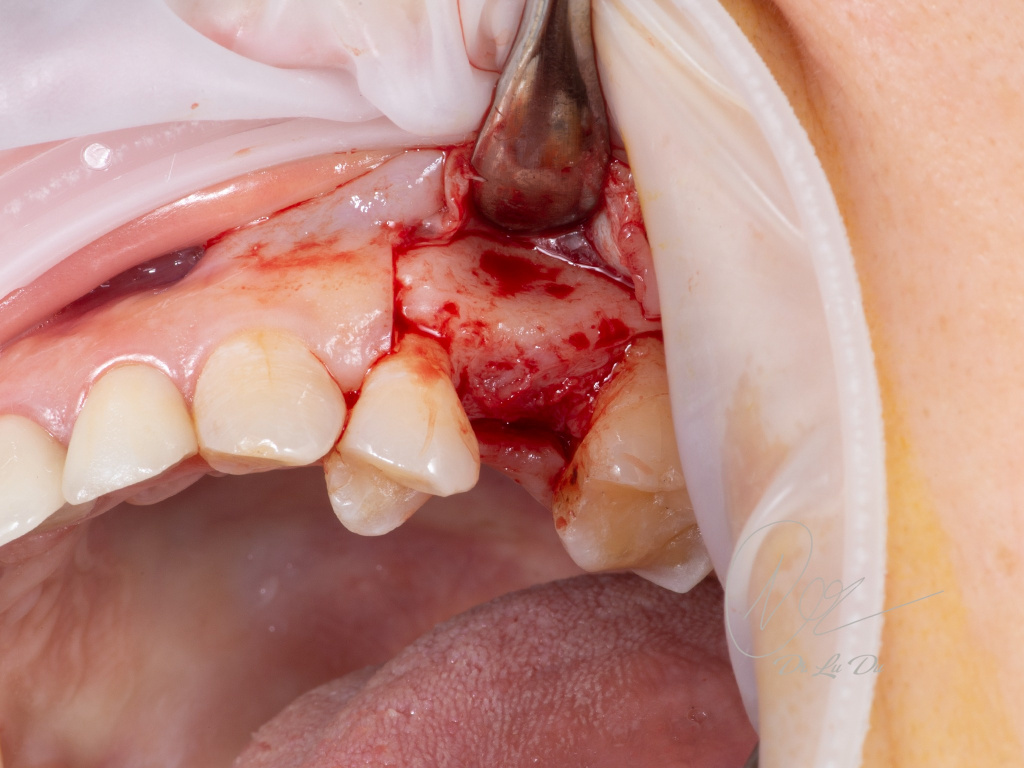

Имплантация AnyRidge с двусторонним закрытым синус-лифтингом.

Осложнения: правосторонний гайморит.

Кейс MINEC: Dr Lu Du